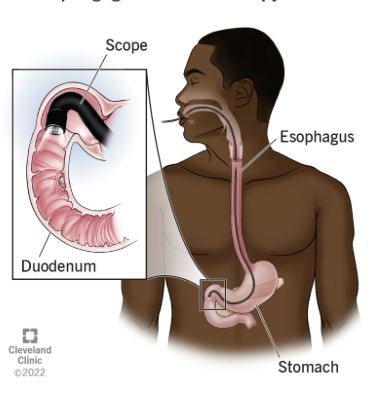

Esophagogastroduodenoscopy (EGD)

Which imaging to assess the upper GI tract including esophagus, stomach, and duodenum looking for ulceration?